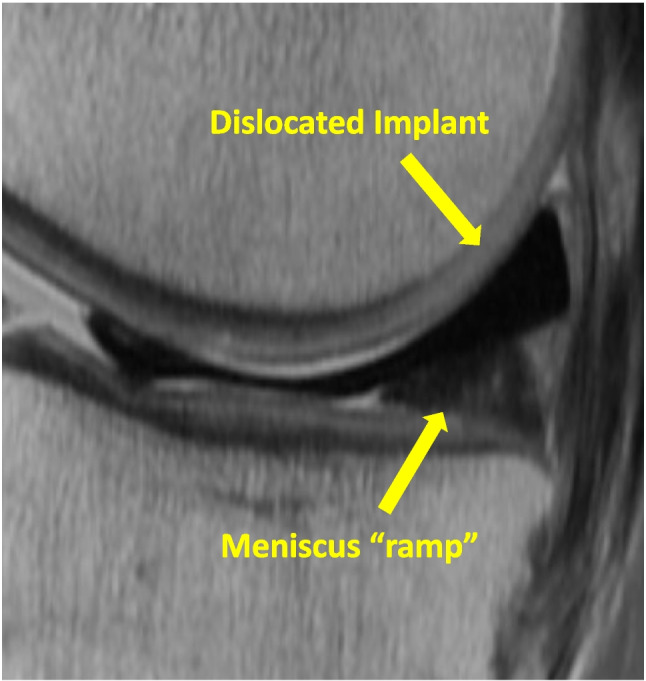

Purpose of review: Meniscectomy alters knee function and known to be associated with an increased incidence of knee arthritis. Several methods and materials have been tried to replicate the function of a meniscus. One is a polycarbonate-urethane synthetic medial meniscus implant labeled as NUsurface. It is a non-anchored implant that is meant to replace the native meniscus. This article is intended to give an overview of the NUsurface implant and the experience to date.

Recent findings: The NUsurface implant is not intended to be a substitute for arthroplasty but has indications similar to meniscal allografts. It has had both prospective double armed and single armed prospective studies. Follow up at the 2-year mark has shown the implant can be successful in decreasing patients' pain and improving function. However, the reoperation rate has been high with a little over a 1/3 requiring an additional procedure and 30% requiring implant exchanged. With improved surgical technique and knowledge of contributing anatomic variables, the reoperation rate has been decreased by half. The synthetic medial meniscus implant NUsurface is able to improve the quality of life in select patients that are symptomatic after meniscectomy. The reoperation rate is of concern but it is decreasing as we refine the variables contributing to the high rate.